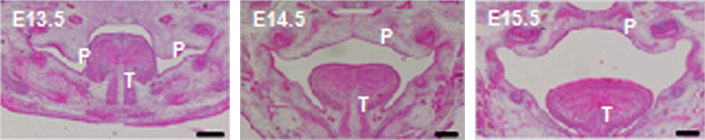

4.口唇裂口蓋裂の病態解明に関する基礎的研究

口唇裂口蓋裂は多因子疾患であり、その発症要因はいまだ明らかになっていない。

遺伝的要因となる疾患感受性遺伝子について、ヒトの血液から採取したDNAを用いたSNP(遺伝子多型)解析、マウスを用いた遺伝子機能解析の両面からアプローチしている。

正常なマウス口蓋の発生

口蓋癒合過程の途中で、遺伝子の機能異常が起こると口蓋裂を発症する